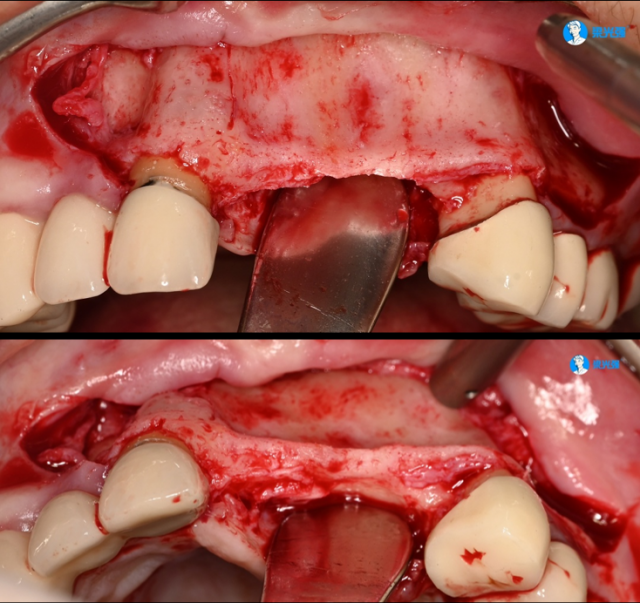

病例展示一

微信图片_2025-07-14_175826_280.jpg

微信图片_2025-07-14_180149_762.jpg